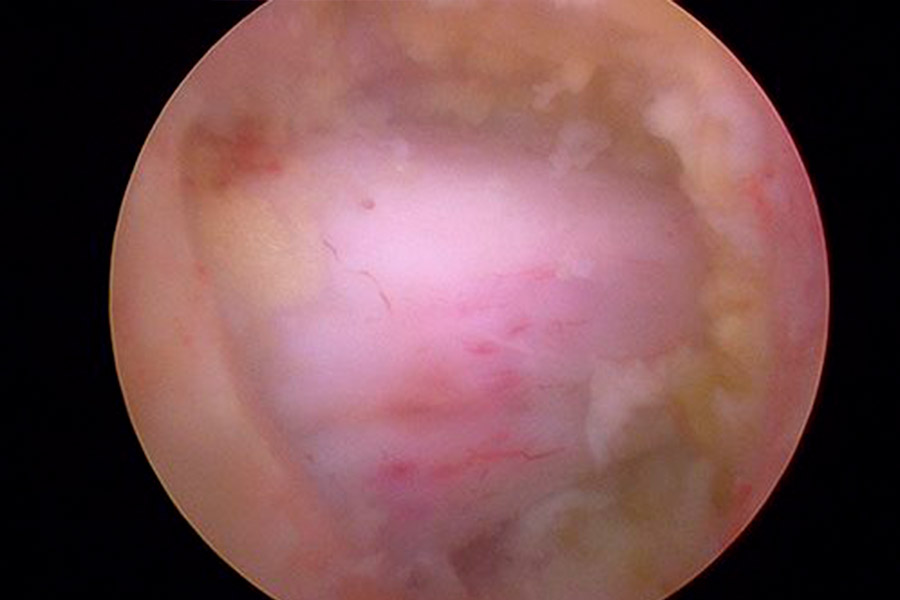

Caso clínico: endoscopia de columna multinivel L4L5 y L5S1

Durante la intervención quirúrgica, se abordarán los dos niveles mediante la técnica de endoscopia de columna.